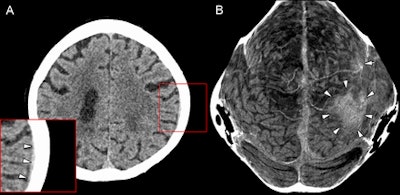

Figure A is a transverse section of a cranial CT image from a 58-year-old woman with a thin subdural hematoma (arrowheads) in the left parietal and temporal region. Lower left corner shows magnification. Figure B is a thin curved MIP of the skull vault. Arrowheads point to the large hematoma, while the single arrow in the left frontal region refers to a smaller hematoma. Image courtesy of Radiology.

Figure A is a transverse section of a cranial CT image from a 58-year-old woman with a thin subdural hematoma (arrowheads) in the left parietal and temporal region. Lower left corner shows magnification. Figure B is a thin curved MIP of the skull vault. Arrowheads point to the large hematoma, while the single arrow in the left frontal region refers to a smaller hematoma. Image courtesy of Radiology.Retrospective evaluation